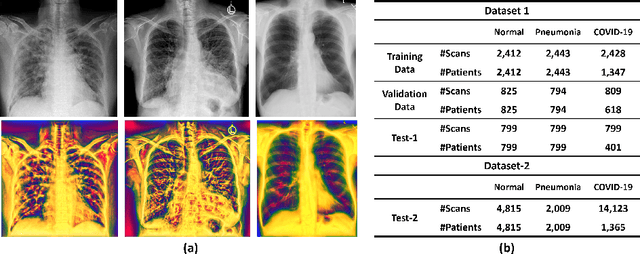

The role of chest X-ray (CXR) imaging, due to being more cost-effective, widely available, and having a faster acquisition time compared to CT, has evolved during the COVID-19 pandemic. To improve the diagnostic performance of CXR imaging a growing number of studies have investigated whether supervised deep learning methods can provide additional support. However, supervised methods rely on a large number of labeled radiology images, which is a time-consuming and complex procedure requiring expert clinician input. Due to the relative scarcity of COVID-19 patient data and the costly labeling process, self-supervised learning methods have gained momentum and has been proposed achieving comparable results to fully supervised learning approaches. In this work, we study the effectiveness of self-supervised learning in the context of diagnosing COVID-19 disease from CXR images. We propose a multi-feature Vision Transformer (ViT) guided architecture where we deploy a cross-attention mechanism to learn information from both original CXR images and corresponding enhanced local phase CXR images. We demonstrate the performance of the baseline self-supervised learning models can be further improved by leveraging the local phase-based enhanced CXR images. By using 10\% labeled CXR scans, the proposed model achieves 91.10\% and 96.21\% overall accuracy tested on total 35,483 CXR images of healthy (8,851), regular pneumonia (6,045), and COVID-19 (18,159) scans and shows significant improvement over state-of-the-art techniques. Code is available https://github.com/endiqq/Multi-Feature-ViT